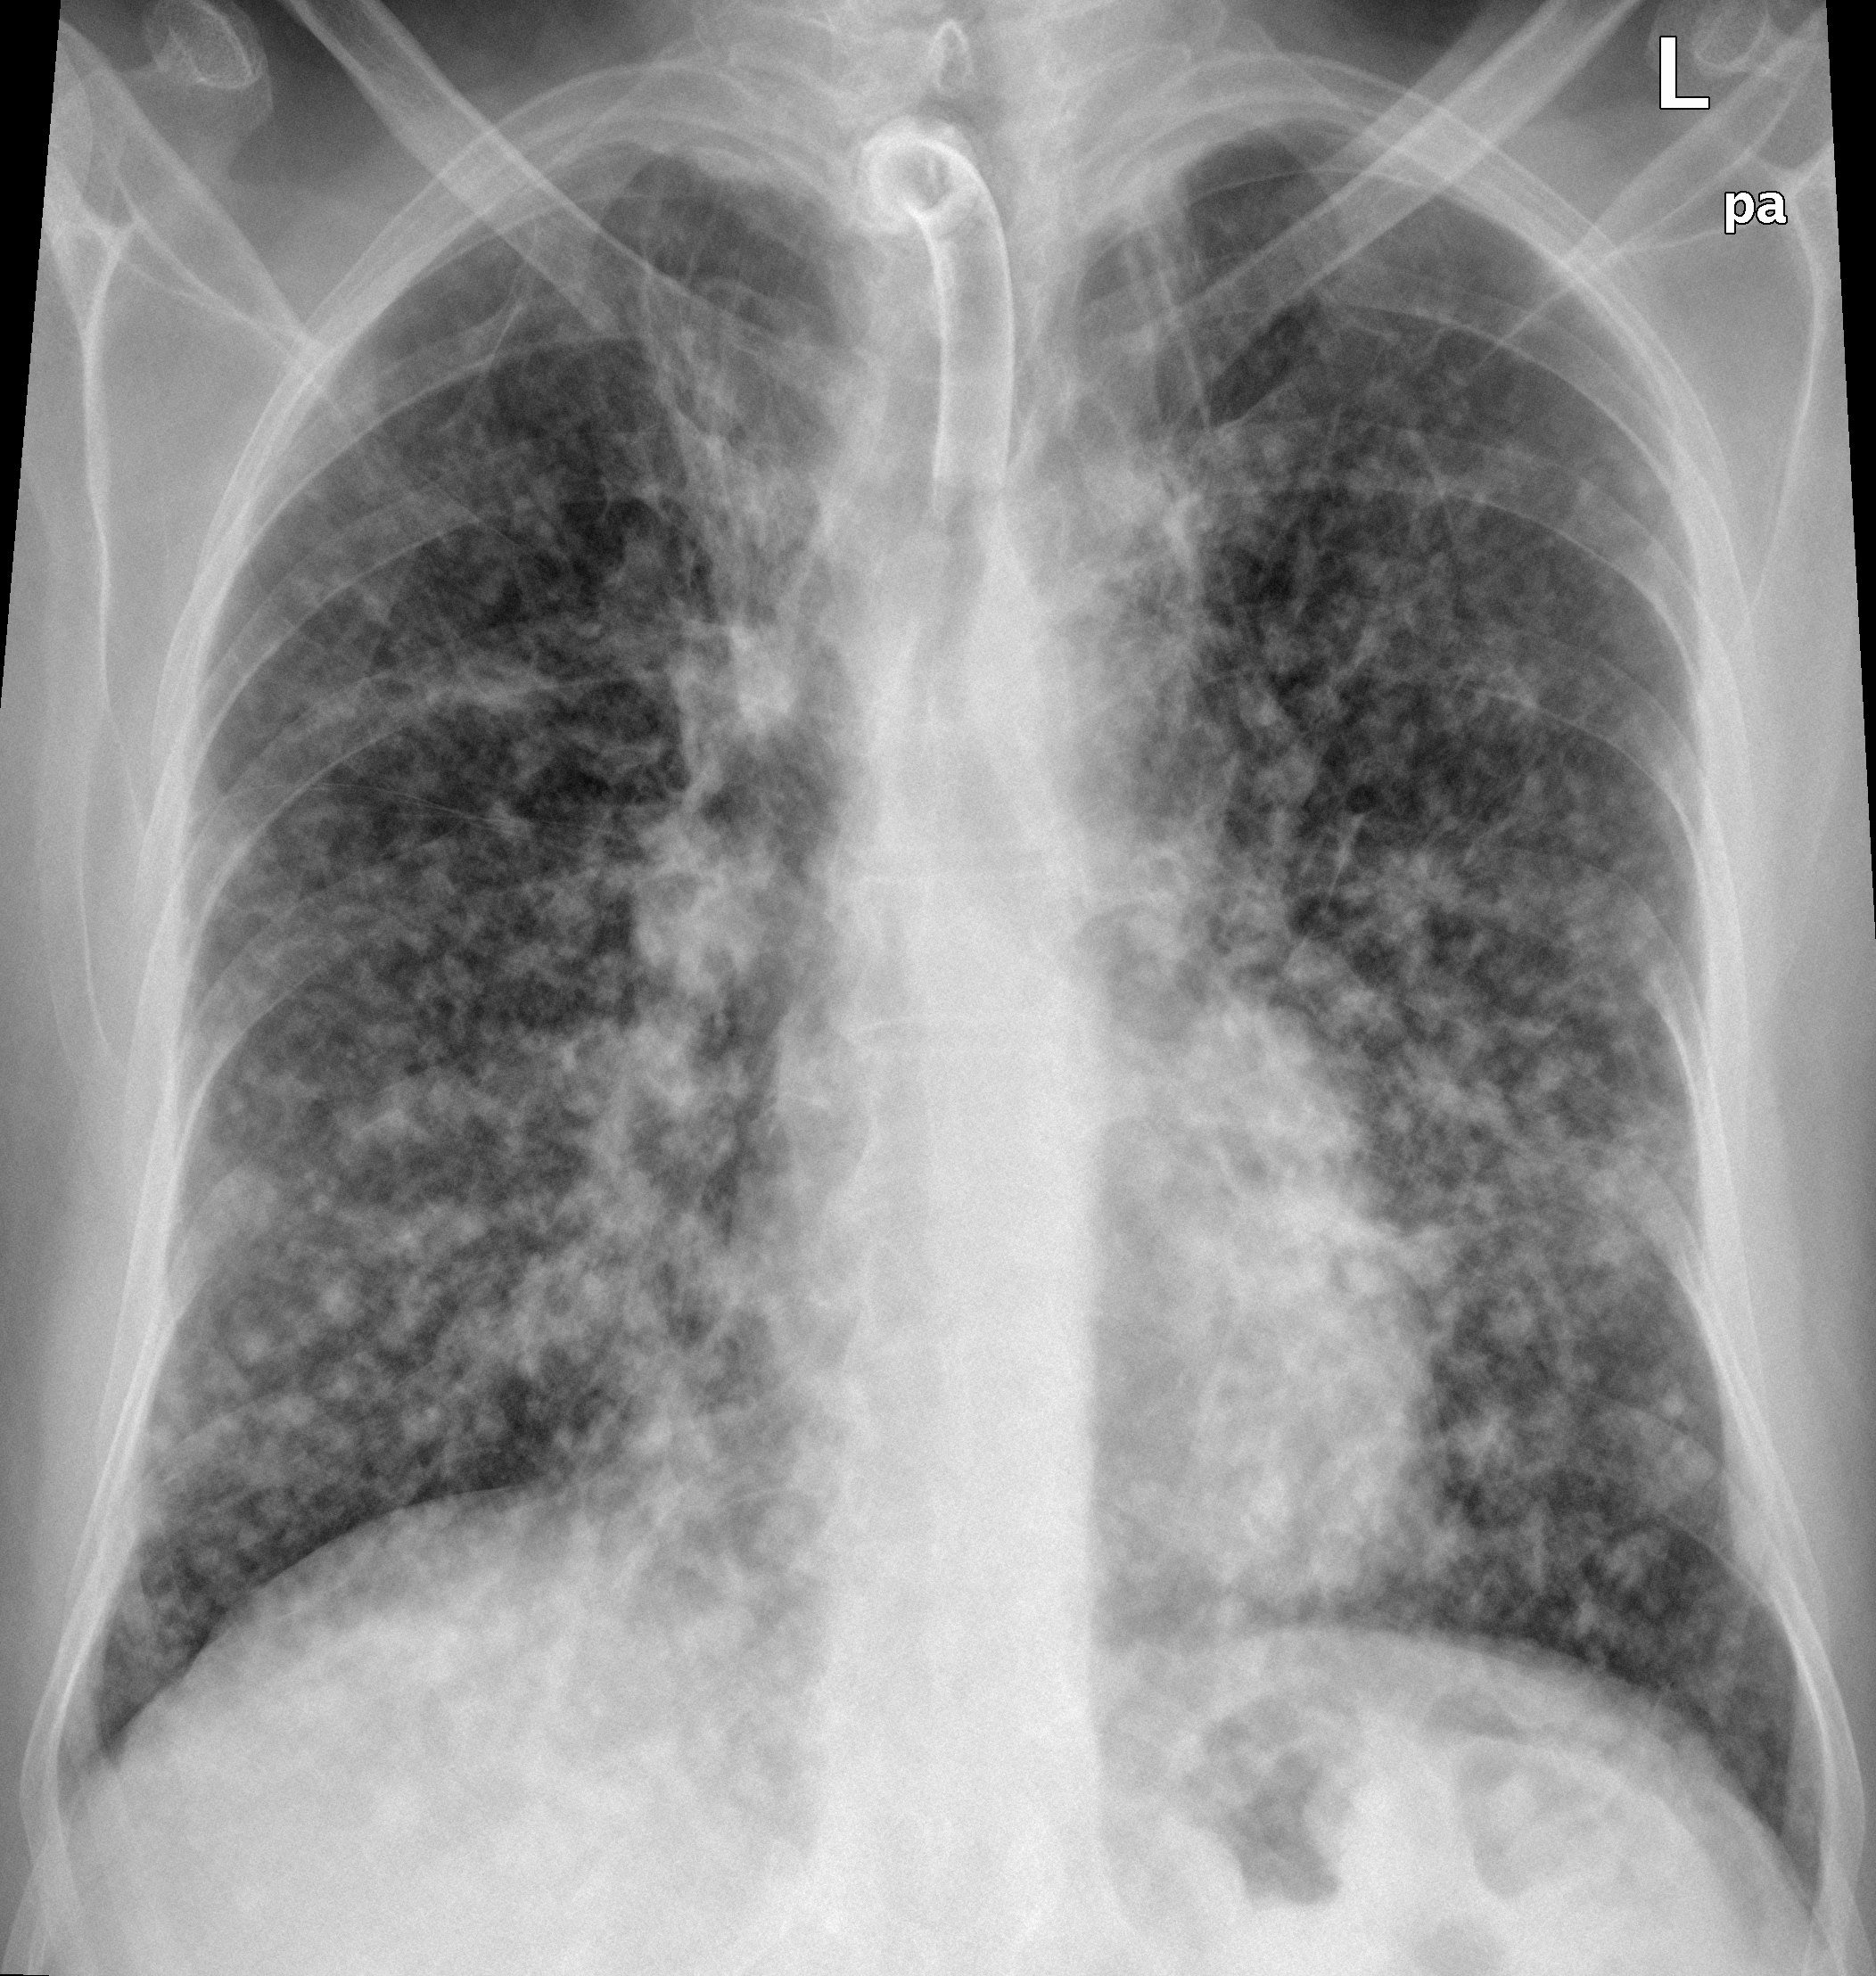

Снимок легких при туберкулезе является важным методом диагностики этого заболевания. На рентгеновских снимках можно увидеть изменения в легких, которые свойственны туберкулезу.

Диссеминированный туберкулез на рентгенограмме

Милиарный туберкулез рентген

Диссеминированный туберкулез рентген

Милиарный туберкулез рентген

Милиарный туберкулез рентген

Острый диссеминированный туберкулёз лёгких рентген

Милиарный туберкулез рентген

Милиарный туберкулез рентген

Диссеминированный туберкулёз лёгких рентген

Милиарный диссеминированный туберкулез

Фотографии снимков легких при туберкулезе

В данной статье представлены многочисленные фотографии снимков легких при туберкулезе, чтобы помочь вам понять, как выглядят изменения легких на рентгеновских снимках при этом заболевании.